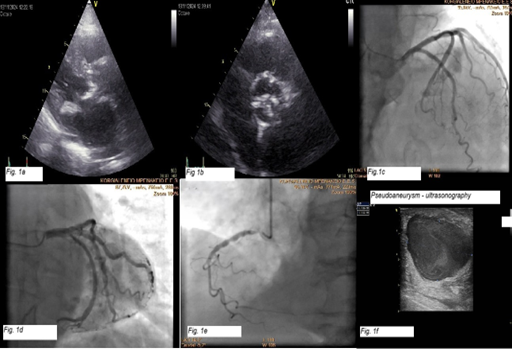

An 81-year-old woman was admitted with dyspnea and irregular heartbeat due to atrial fibrillation with a rapid ventricular response. Echocardiography showed preserved left ventricular ejection fraction, severe aortic stenosis (paradoxical low flow-low gradient), and moderate mitral stenosis (Figure 1A and B). Coronary angiography revealed no significant coronary artery disease (Figure 1C-E).

Two weeks later, a soft, painless, non-inflammatory mass was noted at the radial puncture site. Doppler ultrasound revealed a 3.9 × 2.3-cm pseudoaneurysm with turbulent flow (Figure 1F, Video). Ultrasound-guided compression was attempted but was unsuccessful because of the size of the lesion. Surgical consultation was sought, and the pseudoaneurysm was excised following brachial artery control and radial artery ligation. The patient's postoperative recovery was uneventful, and full healing was confirmed at the 2-week follow-up (Figure 2).